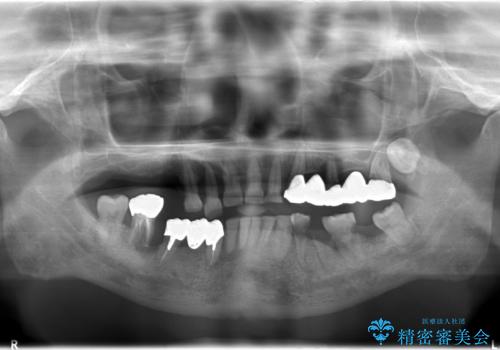

虫歯だらけ、歯周病 崩壊した口腔の再建 フルマウスリコンストラクション

- 歯周外科・インプラント・顕微鏡下根管治療などを含んだ総合的な治療を計画した。

様々な治療手段を高いレベルで同時に併行して行うことが必要でした。

かみ合わせの力が非常に強く、夜間の歯ぎしり・食いしばりもひどかったため、奥歯はメタルオクルーザルの設計でかぶせ物を製作しています。

インプラントの種類:Bicon / Zimmer spline